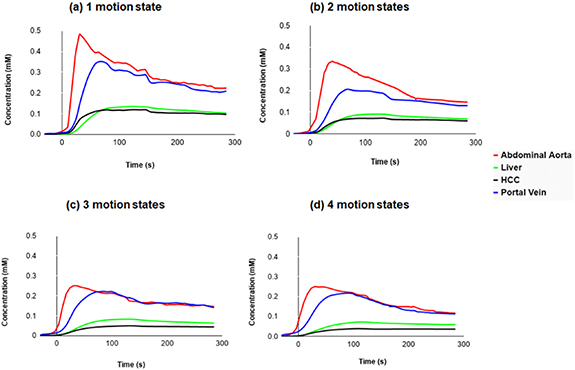

Figure 10 represents global enhancement curves for the portal vein, the liver, the abdominal aorta and the tumor from data reconstructed with increasing number of motion states (1–4) and same number of spokes. The HCC enhancement clearly occurs before the liver's one in the case of 1 and 2 motion states.

Figure 10. Global perfusion curves for the 22 tumors, demonstrating the increased difference between liver and HCC.

Download figure:

Standard image High-resolution imageComparison of all perfusion parameters between different numbers of phases is summarized in table 4 as mean ± SD. Time to peak (TTP) did not significantly change with decreasing number of motion states. The normalized maximum intensity time ratio (nMITR), the peak enhancement ratio (PER) (p < 0.05), and the tumor arterial fraction increased with decreasing number of motion states (p < 0.05) while the transfer constant from the portal venous plasma to the surrounding tissue (Kp) significantly decreased (p < 0.05).

As shown in figure 10, we can observe that a free breathing acquisition with radial k-space acquisition provides organ motion robustness and uniformity in temporal resolution, thus allowing time intensity curve continuous assessment including the arterial peak. Before the intersection of the tumor and liver curves, HCC enhancement clearly occurs before the liver enhancement due to high arterialization of the tumor.

For the arterial enhancement, the normalized maximum intensity time ratio and peak enhancement ratio and tumor arterial fraction increased with decreasing number of motion states while the transfer constant from the portal venous plasma to the extravascular space significantly decreased.

The concentration increases by reducing the number of motion states. Therefore, the images reconstructed with 1 and 2 motion states show the highest concentration for the enhancement arterial curve (≈0.5 mm and 0.3 mm respectively) with higher temporal resolution. While those reconstructed with 3 and 4 motion states were almost the same by representing a lower concentration (≈0.25 mm) of the unclear arterial enhancement peak due to the lower temporal resolution.